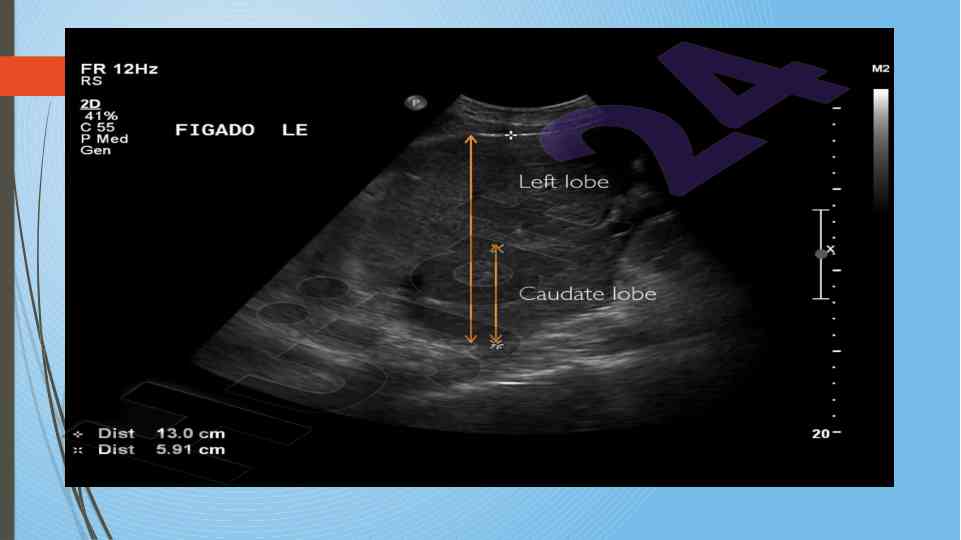

Диссертатсия давомида сурункали гепатитларнинг ультратовуш ташхиси ва этилогиясини ўрганиш. Аутоиммун ва ноалкоголь гепатитларнинг хусусиятлари таҳлил қилинган.